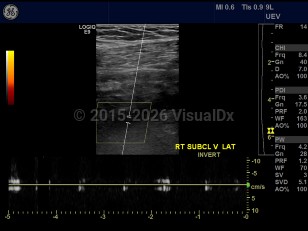

Subclavian vein thrombosis

A blood clot occurring in the subclavian vein, which leads to the brachiocephalic vein and the heart. Thrombi occur more commonly in the right side. Symptoms are primarily pain and edema of the upper extremity, neck, and face. Pulmonary emboli are a life-threatening complication of subclavian vein thrombosis. Many cases are associated with use of a central venous catheter. Other predisposing factors include hypercoagulable disorders and malignancy. Paget-von Schroetter syndrome is a rare cause of subclavian vein thrombosis. It presents in young, healthy patients after exercise. It is caused by a narrow thoracic outlet. Treatment typically consists of anticoagulation, extremity elevation, and local heat application.